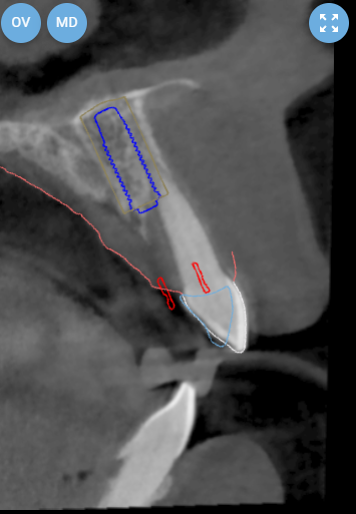

Pre-operative planning was performed using the DICOMLAB digital planning platform. The workflow included a pre-operative CBCT scan of the upper jaw and a digitalintraoral scan.

These datasets were merged within the DICOMLAB software to allow prosthetically driven implant planning.

Planned implant:

DSI Conical Implant - 4.3 mm diameter, 13 mm length.

A custom surgical guide was fabricated using the DICOMLAB open platform, which allows surgical guide production for most implant systems.